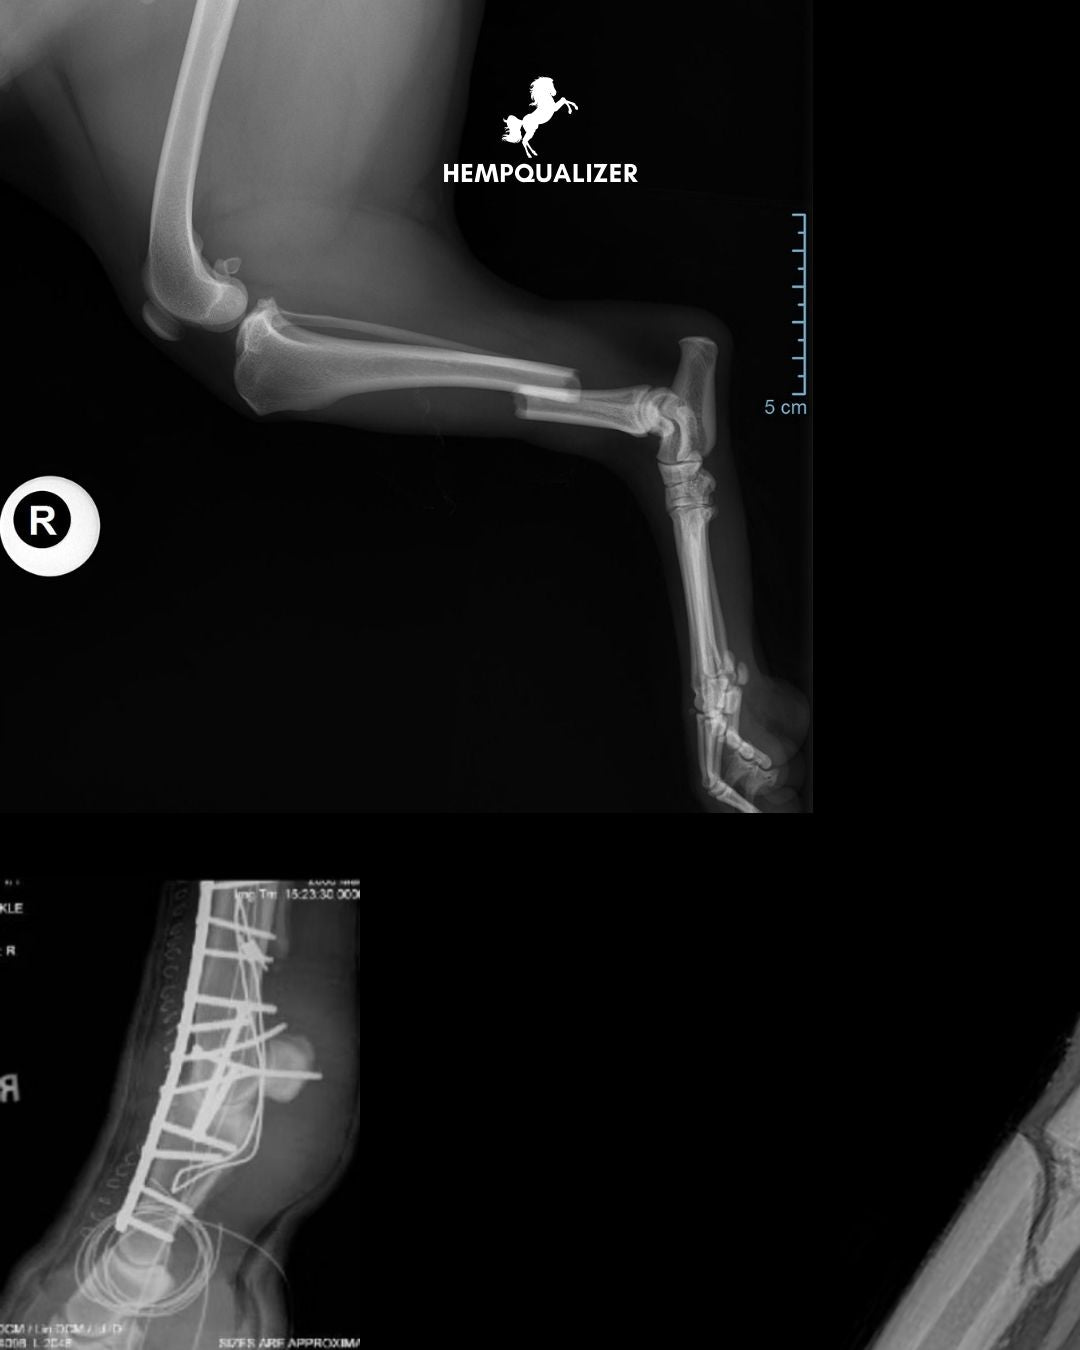

Dorosły koń waży 500–600 kg, a ten ogromny ciężar spoczywa na czterech smukłych kończynach. Dla porównania – kość śródręcza (czyli tzw. „cannon bone”) ma zaledwie ok. 2,5–3 cm średnicy. Przy złamaniu niemalże próba podparcia się na uszkodzonej kończynie prowadzi do dramatycznych uszkodzeń tkanek i dalszych powikłań.

Poniżej stawu nadgarstkowego (przednie kończyny) i skokowego (tylne) nie ma mięśni – są tam tylko kości, ścięgna i więzadła. Oznacza to, że kość nie jest niczym chroniona ani stabilizowana – złamania szybko stają się otwarte, a ryzyko infekcji rośnie błyskawicznie.

Zewnętrzna warstwa tkanek w dolnych partiach kończyn jest bardzo cienka. Uszkodzenie kości może przerwać dopływ krwi i prowadzić do martwicy (tzw. sekwestrów), które łatwo ulegają zakażeniu. W takich warunkach leczenie staje się ekstremalnie trudne.

Kości są cienkie, siły – ogromne. Śruby i płyty muszą znosić nawet 150 kg obciążenia na każdej nodze, a i tak często dochodzi do ich obluzowania, infekcji czy ponownego przemieszczenia odłamów. Leczenie wymaga chirurgii najwyższego poziomu – i nadal nie zawsze kończy się sukcesem.